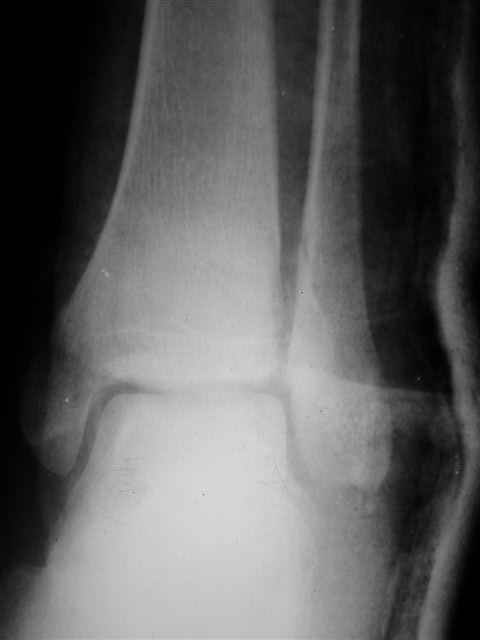

Отправитель: Evgueny Tschekashkin 16 Декабрь 2004, 09:24

В первом письме я упомянул о закрытом повреждении правого голеностопного сустава, эверсионно-пронационный механизм травмы - перелом внутренней лодыжки( поперечный, на уровне суставной щели) и отрывной перелом бугорка Chaput. После обработки открытых переломов бедра и большеберцовой кости в эту же сессию перелом внутренней лодыжки фиксировал двумя расходящимися спицами, бугорок Chaput двумя тягловыми винтами 3,5 мм. Раны заживают благополучно. Учитывая повреждение наружной группы мышц, активное разгибание в голеностопном суставе ограничено. Пассивная + пассивно-активная мобилизация голеностопного сустава с физиотерапевтом.

Каких-либо вопросов по лечению травмы голеностопного сустава у меня не возникло,поэтому о дальнейших деталях лечения я не упоминал.

(Если вы заинтересовались, то Рг граммы представлю)

Я предупреждал, что ничего сверхъестественного. Каюсь, что одна из спиц прошла несколько дальше, чем нужно было, но главное - перелом стабилизирован и больной работает суставом в полном объёме, несмотря на представленную раннее травму коленного сустава.